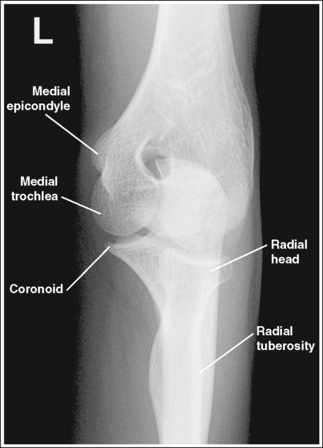

See Figure 4-66 and Box 4-18.

The elbow is positioned in an AP projection. The medial and lateral humeral epicondyles are demonstrated in profile at the extreme medial and lateral edges of the distal humerus, and the radial head is superimposed over the lateral aspect of the proximal ulna by approximately 0.25 inch (0.6 cm). The coronoid process is demonstrated on end.

• An AP projection of the elbow is obtained by supinating the patient's hand and externally rotating the forearm and humerus until an imaginary line drawn between the humeral epicondyles is parallel with the IR (Figure 4-67). This positioning places the proximal radius anterior to the ulna.

• Detecting elbow rotation. Rotation of the elbow is a result of poor humeral epicondyle positioning and can be identified on an image when (1) the epicondyles are not visualized in profile, (2) the radial head is demonstrated with more or less than 0.25 inch (0.6 cm) superimposition of the ulna, and (3) the coronoid process is seen in profile. The smaller, lateral humeral epicondyle is more sensitive to rotation, moving out of profile with only a slight degree of elbow rotation. If the epicondyles are not demonstrated in profile, evaluate the degree of radial head superimposition of the ulna to determine how to reposition for an AP projection. If more than 0.25 inch (0.6 cm) of radial head is superimposed over the ulna, the elbow has been internally rotated (see Image 74). If less than 0.25 inch (0.6 cm) of the radial head is superimposed over the ulna, the elbow has been externally rotated (see Images 75 and 76).